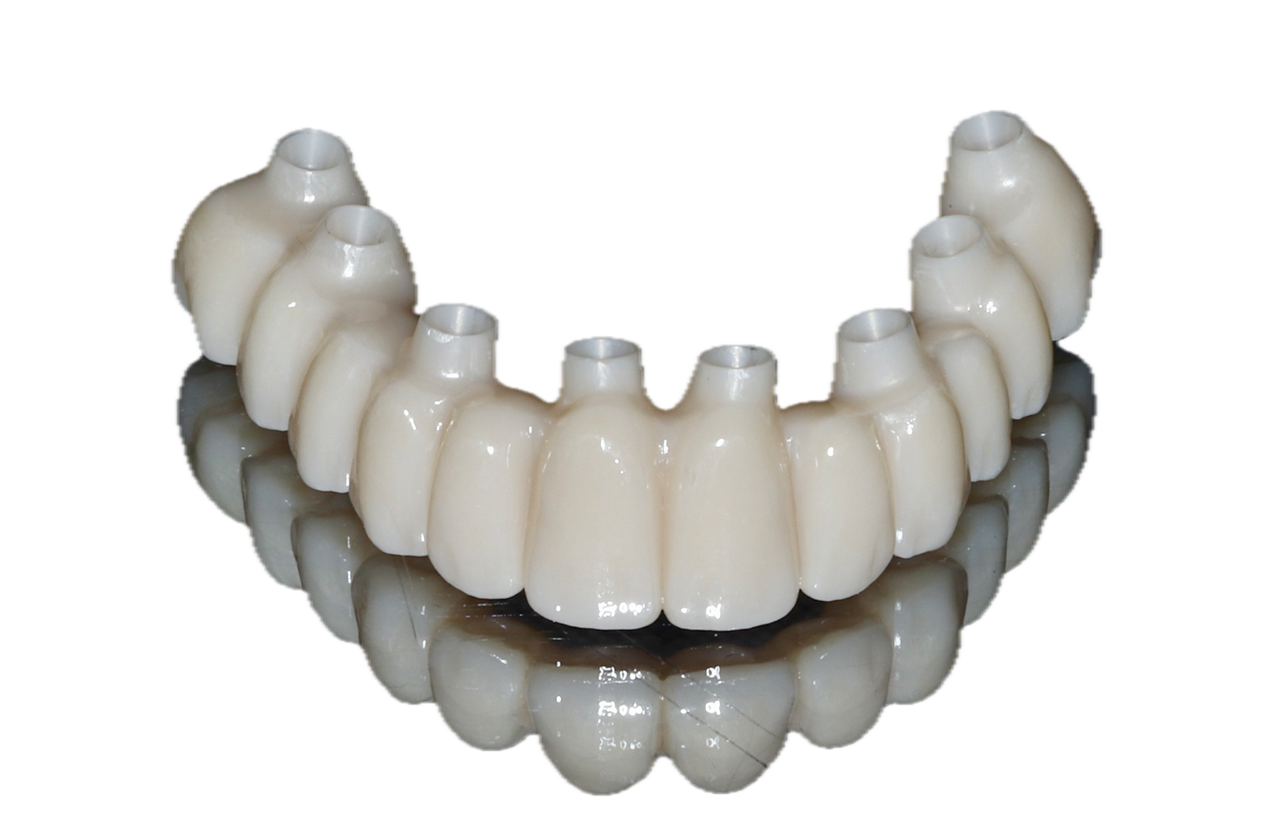

(14.) Examples of the different types of fixed full-arch prostheses described by the Misch classification system, including an FP1 crown only restoration, an FP2 “long teeth” restoration, and an FP3 restoration that incorporates a pink component, respectively.

Figure 14

(15.) Examples of the different types of fixed full-arch prostheses described by the Misch classification system, including an FP1 crown only restoration, an FP2 “long teeth” restoration, and an FP3 restoration that incorporates a pink component, respectively.

Figure 15

(16.) Examples of the different types of fixed full-arch prostheses described by the Misch classification system, including an FP1 crown only restoration, an FP2 “long teeth” restoration, and an FP3 restoration that incorporates a pink component, respectively.

Figure 16

When a fixed prosthesis is desired, the decision regarding what type warrants careful consideration. The Misch system classifies fixed full-arch prostheses into three categories: FP1, FP2, and FP3.11 FP1 denotes a fixed prosthesis that replaces only the crown forms of missing teeth with no pink material to replace the gingiva. This type of prosthesis is indicated for edentulous arches that demonstrate minimal loss of hard and soft tissue (Figure 14). FP1 prostheses include bridges where artificial teeth are supported by natural teeth or implants. In contrast, FP2 prostheses replace the anatomical crown and root forms of missing teeth (Figure 15). These are intended to address edentulous arches with minimal to moderate loss of hard and soft tissue. And finally, FP3 protheses replace the anatomical crown and a portion of the soft tissue, incorporating pink material to restore the full complement of teeth and gingival tissues for arches that demonstrate a moderate to advanced loss of hard and soft tissue (Figure 16). Each option presents distinct benefits and considerations regarding function, esthetics, health, and long-term maintenance. By carefully assessing these factors, dental professionals can customize treatment plans to accommodate the individual needs and preferences of all patients. For example, addressing a smile that exhibits vertical maxillary excess may require extensive bone reduction to conceal the transition zone of an FP3 prosthesis, whereas an FP1 solution may require no or only minor bone removal, which may be more suitable for the patient and clinician.